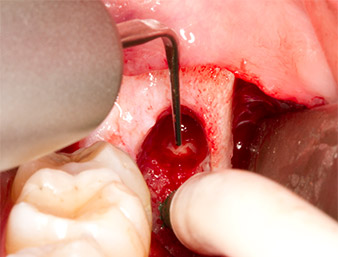

A continuación, se utilizó un inserto para la retirada de los sedimentos periodontales (Piezomed P1) y se amplió mínimamente el surco periodontal del resto radicular (figura 8).

El mismo inserto activado se introdujo en el canal radicular y aflojó el fragmento gracias a sus vibraciones microoscilantes (figuras 9 y 10).

Piezomed P1

Imagen 9: El fabricante recomienda el inserto Piezomed P1 sobre todo para la extracción periodontal de placa, pero también resulta adecuado para propósitos quirúrgicos. En este caso, se colocó en el canal radicular después de una ampliación mínima del surco periodontal.

Imagen 10: Gracias a su estilizado diseño, el inserto puede introducirse en el canal radicular para retirar el resto radicular mediante microoscilaciones (vibraciones).

A continuación, se utilizó el accesorio P1 para retirar de una pieza el resto radicular de aproximadamente seis milímetros de longitud (figura 11).